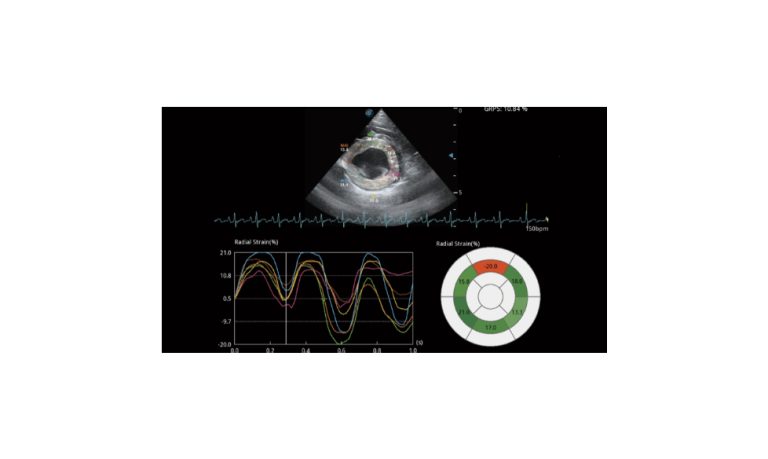

Ultrasound

Wide range of Ultrasound machines that suites a variety of applications from abdominal to rectal scans, we take in consideration how the world is moving towards mobility and mobile applications.

SonoScape Pro Pet E11

Smart Imaging

Introducing the first portable ultrasound with the C-Field+TM platform, redefining diagnostic imaging. Designed for veterinarians, it delivers unmatched clarity, ultra-fast processing, and seamless adaptability for all species. Experience Smart Imaging, Heartfelt Care—anywhere.

Equipped with cutting-edge veterinary software and optimized workflows, it embodies our commitment to Smart Imaging, Heartfelt Care – Wherever Their Journey Leads, with unparalleled performance and adaptability, this innovative system empowers veterinarians to provide exceptional care across all diagnostic applications,